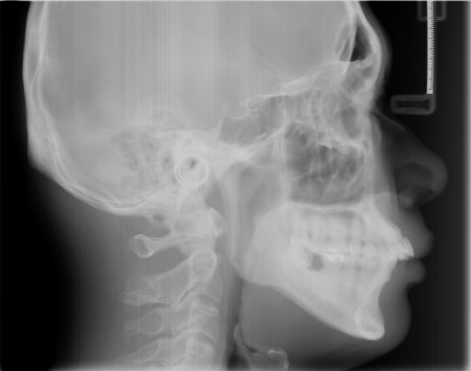

为了让自己更自信,何小姐自行在内地的牙科诊所进行了金属托槽矫正。五个月之间他还一直不能适应矫正器,牙齿连蛋糕和香蕉都咬不动,平时主要吃流食。"为了变美我忍了。"但有一天她突然发现上牙牙列稍有整齐,可是牙骨越来越外突,侧面看过去,口腔有明显外突。"我当时都懵了。"

【矫正失败,嘴型明显外突】